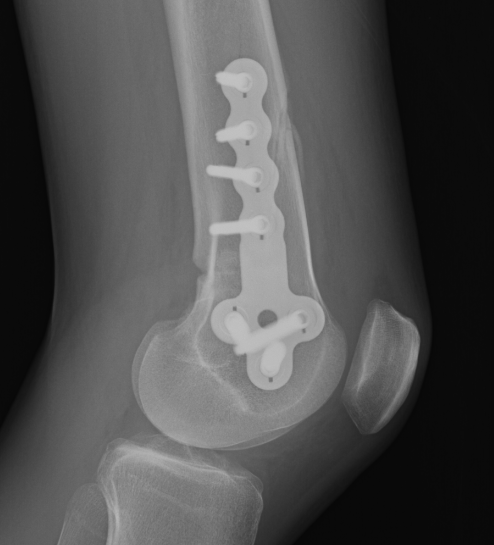

Medial Closing Wedge Osteotomy

Advantages

- lower risk of non union

- better for larger corrections

Disadvantage

- requires two osteotomy cuts

Distal Femoral Osteotomy MedialDFCO medial closing wedge

Technique

Patient supine on a radiolucent table

Surgical approach

- medial longitudinal incision

- identify fascia of vastus medialis and joint capsule

- elevate vastus medialis off medial intermuscular septum leaving cuff of tissue to protect vessels

- Hohmann retractor posteriorly to protect NV bundle

Osteotomy

- insert two K wires for desired wedge

- resect templated wedge

- stop 1 cm short of lateral cortex

- close femoral wedge